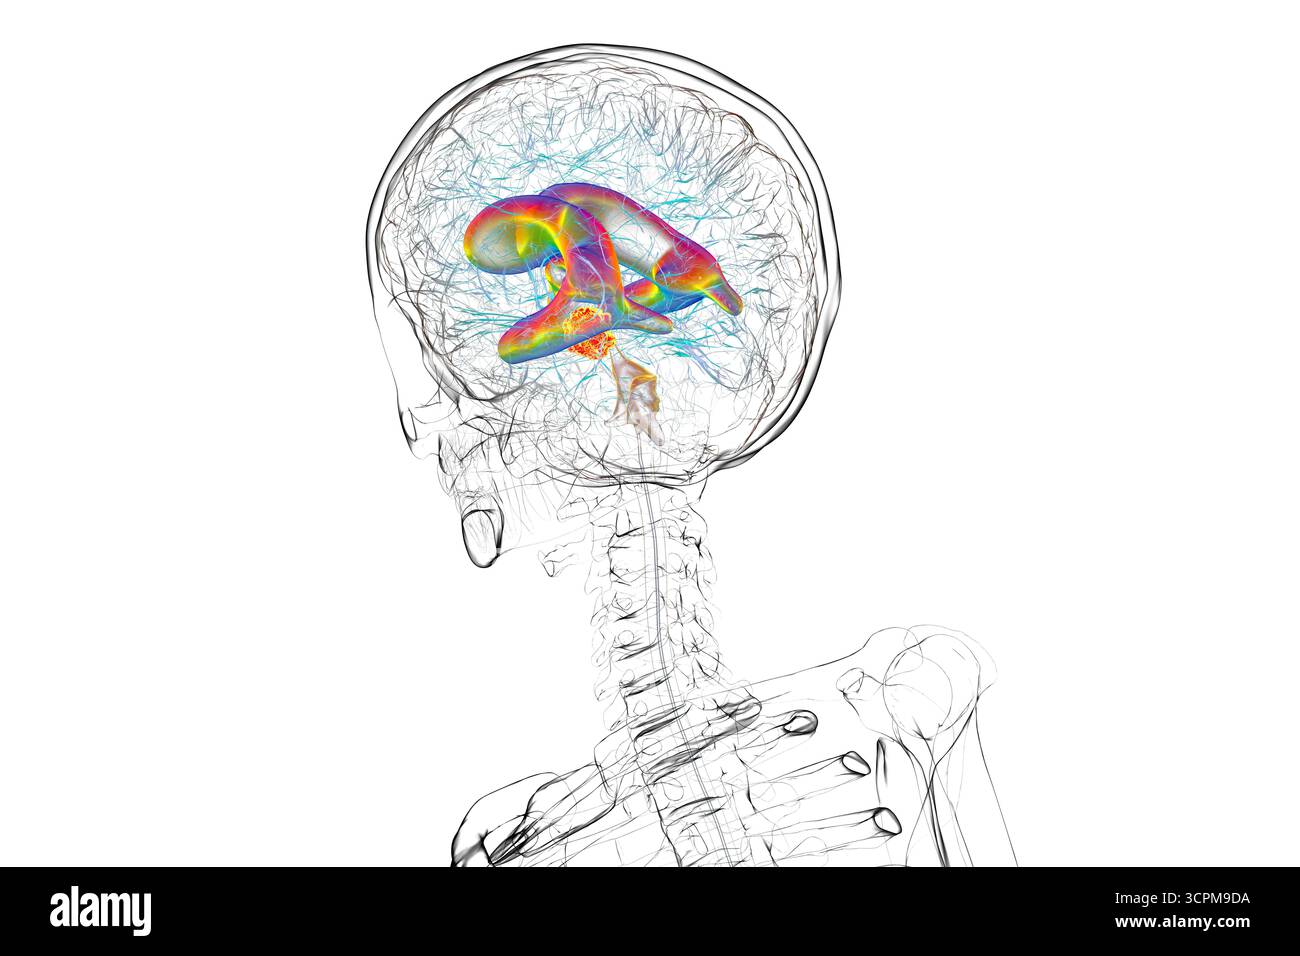

RF3CN8WHP–Illustration des vergrößerten lateralen und dritten Ventrikels des Gehirns (Hydrozephalus), hervorgerufen durch einen Hirntumor, der den Aquädukt des Gehirns komprimiert.

RF3CPM9C1–Illustration des dritten Hirnventrikels, einer lebenswichtigen Komponente des Hirnventrikulärsystems.

RF3CPM9BH–Illustration des dritten Hirnventrikels, einer lebenswichtigen Komponente des Hirnventrikulärsystems.

RF3CPM9BF–Illustration des dritten Hirnventrikels, einer lebenswichtigen Komponente des Hirnventrikulärsystems.

RF3CPM9BE–Illustration des dritten Hirnventrikels, einer lebenswichtigen Komponente des Hirnventrikulärsystems.

RF3CPM9BX–Illustration des dritten Hirnventrikels, einer lebenswichtigen Komponente des Hirnventrikulärsystems.